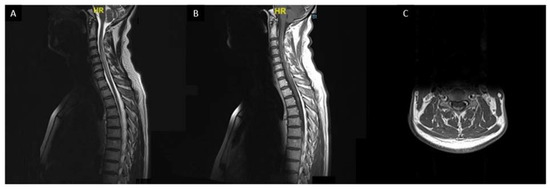

Spinal cord sarcoidosis (SCS) occurs in less than 1% of all patients [167,168,169]. In comparison with other myelopathies, neurologic pain seems to be more frequent and may be considered as an alarm for early diagnosis of SCS [170]. Sarcoidosis associated myelitis is usually extensive (more than three vertebral levels) with a subacute/progressive onset compared with other myelopathies (vascular, inflammatory, or infectious myelopathies) (Figure 7). A distinct MRI phenotype, with enhancement in subpial and/or meningeal areas, also called “trident sign”, is seen in sarcoidosis-associated myelopathy and can help the diagnosis [171].

Figure 7. Sarcoidosis associated myelitis: (A): T2-weighted sagittal MRI slice showing longitudinally extensive T2 hyperintensity of the cervical and upper thoracic spinal cord associated with a focal T2 hyperintensity at T3 vertebra level; (B,C): T1-weighted post gadolinium sagittal (B) and axial (C) MRI images showing posterior subpial enhancement of the lesions.